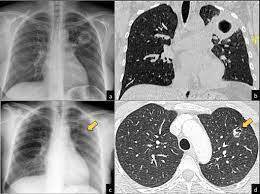

Es una opacidad lineal o en red que ocurre por ocupación de agua, colágeno o enfermedad del intersticio en la barrea alveólo-capilar:

Patrón intersticial o reticular

¿Cómo se ve el patrón intersticial o reticular en rx y TC?

Líneas finas o gruesas en los extremos del pulmón

Son las causas más frecuentes del patrón intersticial o reticular: